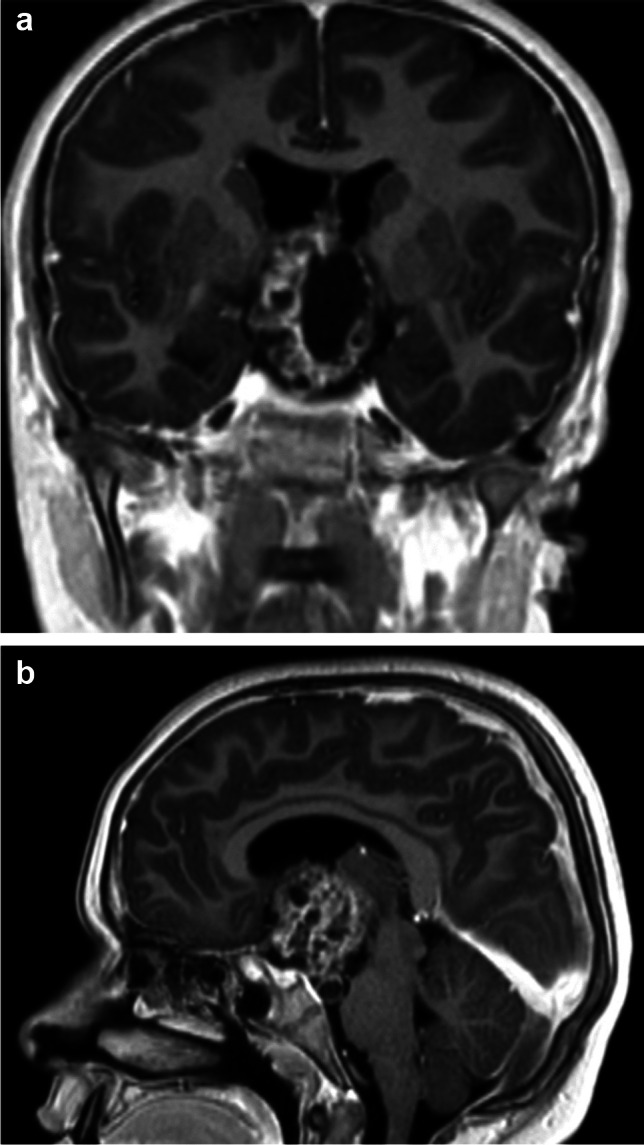

Background: Craniopharyngioma (CP) surgery in children leads to high rate of recurrence, and morbid complications. Transcranial approach is the most frequently proposed surgical technique, but transsphenoidal endoscopic approach is also used. Pre- and post-operative complications of the tumor are well known, but early multidisciplinary management could improve the long-term outcome of these patients. The aim of this study was to analyse the risk factors for pre-and post-operative long-term complications in a series of patients operated with an aggressive removal for CP.

Methods: A retrospective study of 26 children diagnosed with CP was carried out. The surgical total removal was possible in 88% of cases after the revision of the post-operative MRI realized in the first 48 h.

Results: Children with hypothalamic involvement were more likely to have endocrine deficits and to be overweight or obese pre-operatively. They also had a higher risk of early post-operative complications, and late morbidities.

Conclusion: Children with CP and strong hypothalamic involvement, have a higher risk of pre- and post-operative complications but complete removal is associated with a high rate of cure with global good neuropsychological results. Early multidisciplinary post-operative management should be reinforced to improve the long-term outcome but surgery with total removal can insure definitive acceptable clinical results.